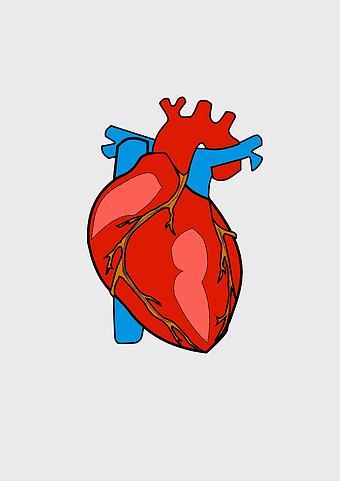

red heart anatomy, human heart drawing, cartoon heart illustration, love and biology, cardiovascular system diagram, medical art depiction, organ structure visualization -

Heart Anatomy Diagram, human heart drawing, realistic heart illustration, cardiovascular system, medical illustration, organ structure, human anatomy study -

human heart anatomy, cardiovascular system illustration, medical heart diagram, heart organ structure, human body organ visuals, anatomical heart drawing, heart health -

human heart diagram, cardiovascular system anatomy, blood vessel chart, free body diagram, circulatory system illustration, medical organ visualization, human anatomy study -

human heart anatomy, cardiac muscle illustration, circulatory system model, heart health visual, cardiovascular organ diagram, medical heart image, visceral structure depiction -

human heart anatomy, red heart illustration, heart organ diagram, heart muscles and valves, cardiovascular system diagram, human body organ chart, anatomical heart structure -

human heart anatomy, superior vena cava illustration, systemic circulation diagram, heart rate visual, cardiovascular system study, medical organ depiction, human body organ reference -

human heart illustration, cardiac anatomy diagram, heart blood vessels, medical organ visuals, cardiovascular system chart, human anatomy study, circulatory system illustration -